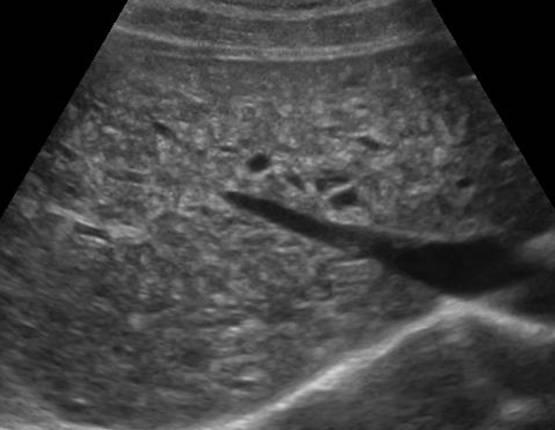

Hamartoma đường mật

» Thông tin: Nam giới – 34 tuổi.

» Lâm sàng: Kiểm tra sức khỏe.